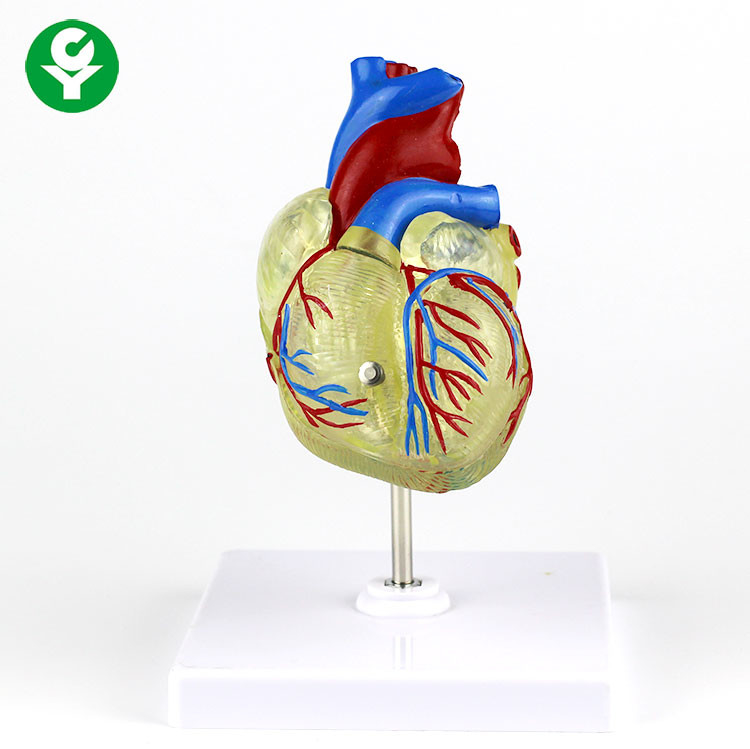

หัวใจมนุษย์ กายวิภาคศาสตร์ ภาพสต็อก – ดาวน์โหลดรูปภาพตอนนี้ – iStock พลาสติกใสหัวใจมนุษย์ทางการแพทย์สำหรับการสาธิต

พลาสติกใสหัวใจมนุษย์ทางการแพทย์สำหรับการสาธิต รูปเวกเตอร์ฟรีเกี่ยวกับหัวใจมนุษย์ PNG , หัวใจ, ชีววิทยา, ไอคอนภาพ PNG …

รักสุดใจ! ช่อช็อกโกแลตให้เธอ รวมไอเดียช่อช็อกโกแลตสื่อรัก มอบให้แฟน แบบจำลองหัวใจมนุษย์ขนาดชีวิตที่มีสีพื้นโปร่งใสโรคหัวใจทางการแพทย์แบบ …

แบบจำลองหัวใจมนุษย์ขนาดชีวิตที่มีสีพื้นโปร่งใสโรคหัวใจทางการแพทย์แบบ … Chocolate Heart, Hand-drawn sketch Chocolate s, brown, food png | PNGEgg

Chocolate Heart, Hand-drawn sketch Chocolate s, brown, food png | PNGEgg แบบจำลองหัวใจมนุษย์ขนาดชีวิตที่มีสีพื้นโปร่งใสโรคหัวใจทางการแพทย์แบบ …

แบบจำลองหัวใจมนุษย์ขนาดชีวิตที่มีสีพื้นโปร่งใสโรคหัวใจทางการแพทย์แบบ … ช็อกโกแลต รูปฟุตบอล เหรียญทอง หัวใจ บรรจุ 60 ชิ้น | Shopee Thailand

Anatomy หัวใจมนุษย์รุ่นพลาสติกทางการแพทย์กายวิภาคหัวใจจัมโบ้รุ่นอวัยวะ … รูปช็อกโกแลตหัวใจพร้อมน้ำเชื่อม PNG , วาเลนไทน์วัน, หัวใจ, วันแห่งความ …

3d Anatomy หัวใจมนุษย์รุ่นพลาสติกทางการแพทย์กายวิภาคหัวใจจัมโบ้รุ่น … หัวใจวิทยาศาสตร์เรื่องกายวิภาคศาสตร์ทางการแพทย์หัวใจมนุษย์รุ่นขาย – Buy …

Anatomy หัวใจมนุษย์รุ่นพลาสติกทางการแพทย์กายวิภาคหัวใจจัมโบ้รุ่นอวัยวะ … ภาพประกอบแบนเวกเตอร์หัวใจมนุษย์ขนาดใหญ่บนพื้นหลังสีขาว ภาพประกอบสต็อก …

หัวใจมนุษย์กายวิภาครุ่นวิทยาศาสตร์การแพทย์รูปแบบการสอน ห้องหัวใจมนุษย์: คำอธิบายโครงสร้างหน้าที่และประเภท

หุ่นจำลองหัวใจมนุษย์ 3d มนุษย์กายวิภาครุ่นหัวใจมนุษย์สำหรับซัพพลายเออร์แบบครบวงจรวิทยาศาสตร์ …

3d มนุษย์กายวิภาครุ่นหัวใจมนุษย์สำหรับซัพพลายเออร์แบบครบวงจรวิทยาศาสตร์ … 3d Anatomy หัวใจมนุษย์รุ่นพลาสติกทางการแพทย์กายวิภาคหัวใจจัมโบ้รุ่น …

3d Anatomy หัวใจมนุษย์รุ่นพลาสติกทางการแพทย์กายวิภาคหัวใจจัมโบ้รุ่น … อวัยวะหัวใจของมนุษย์ | องค์ประกอบกราฟฟิก แบบ PSD ดาวน์โหลดฟรี – Pikbest

หัวใจมนุษย์กายวิภาครุ่นวิทยาศาสตร์การแพทย์รูปแบบการสอน 15 Porch ช็อกโกแลต Fudge แม่พิมพ์ซิลิโคนหัวใจรูปเค้กช็อกโกแลตตกแต่ง DIY …

อุปกรณ์การศึกษากายวิภาคศาสตร์รุ่นหัวใจมนุษย์รุ่นสำหรับโรงเรียนขนาดชีวิต … วิธีทำ “นามะช็อกโกแลต” ของฝากยอดฮิตจากญี่ปุ่น อร่อยหรูดูแพง แต่ทำง่าย …

In-306 3d กายวิภาคศาสตร์หัวใจมนุษย์รูปแบบทางการแพทย์พลาสติกกายวิภาค … บอลลูนหัวใจมนุษย์ Angioplasty เวกเตอร์ ภาพประกอบ ภาพประกอบสต็อก – ดาวน์ …

โรงงานโดยตรงขาย Anatomy หัวใจมนุษย์การฝึกอบรมชุดอวัยวะภายในรุ่น – Buy …